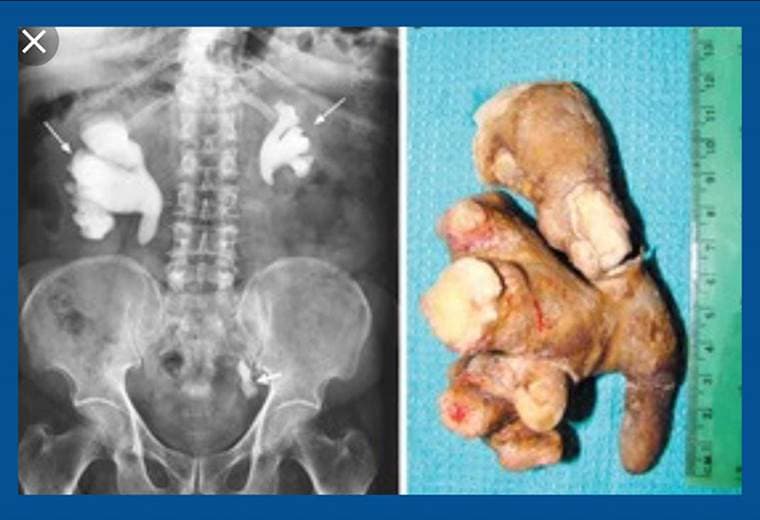

¿Por qué se forman las piedras en los riñones?

Dicen que uno de los dolores más fuertes que podemos experimentar es el de las piedras en los riñones.

El 10% de la población, es decir diez de cada cien personas, las va a presentar en algún momento de su vida y aunque hemos escuchado que hay tratamientos para "deshacerlas", lo cierto es que solo a través de cirugía se pueden eliminar.

Hoy el urólogo Mario González nos habla sobre un láser, que, sin dejar cicatrices, elimina las piedras en los riñones.